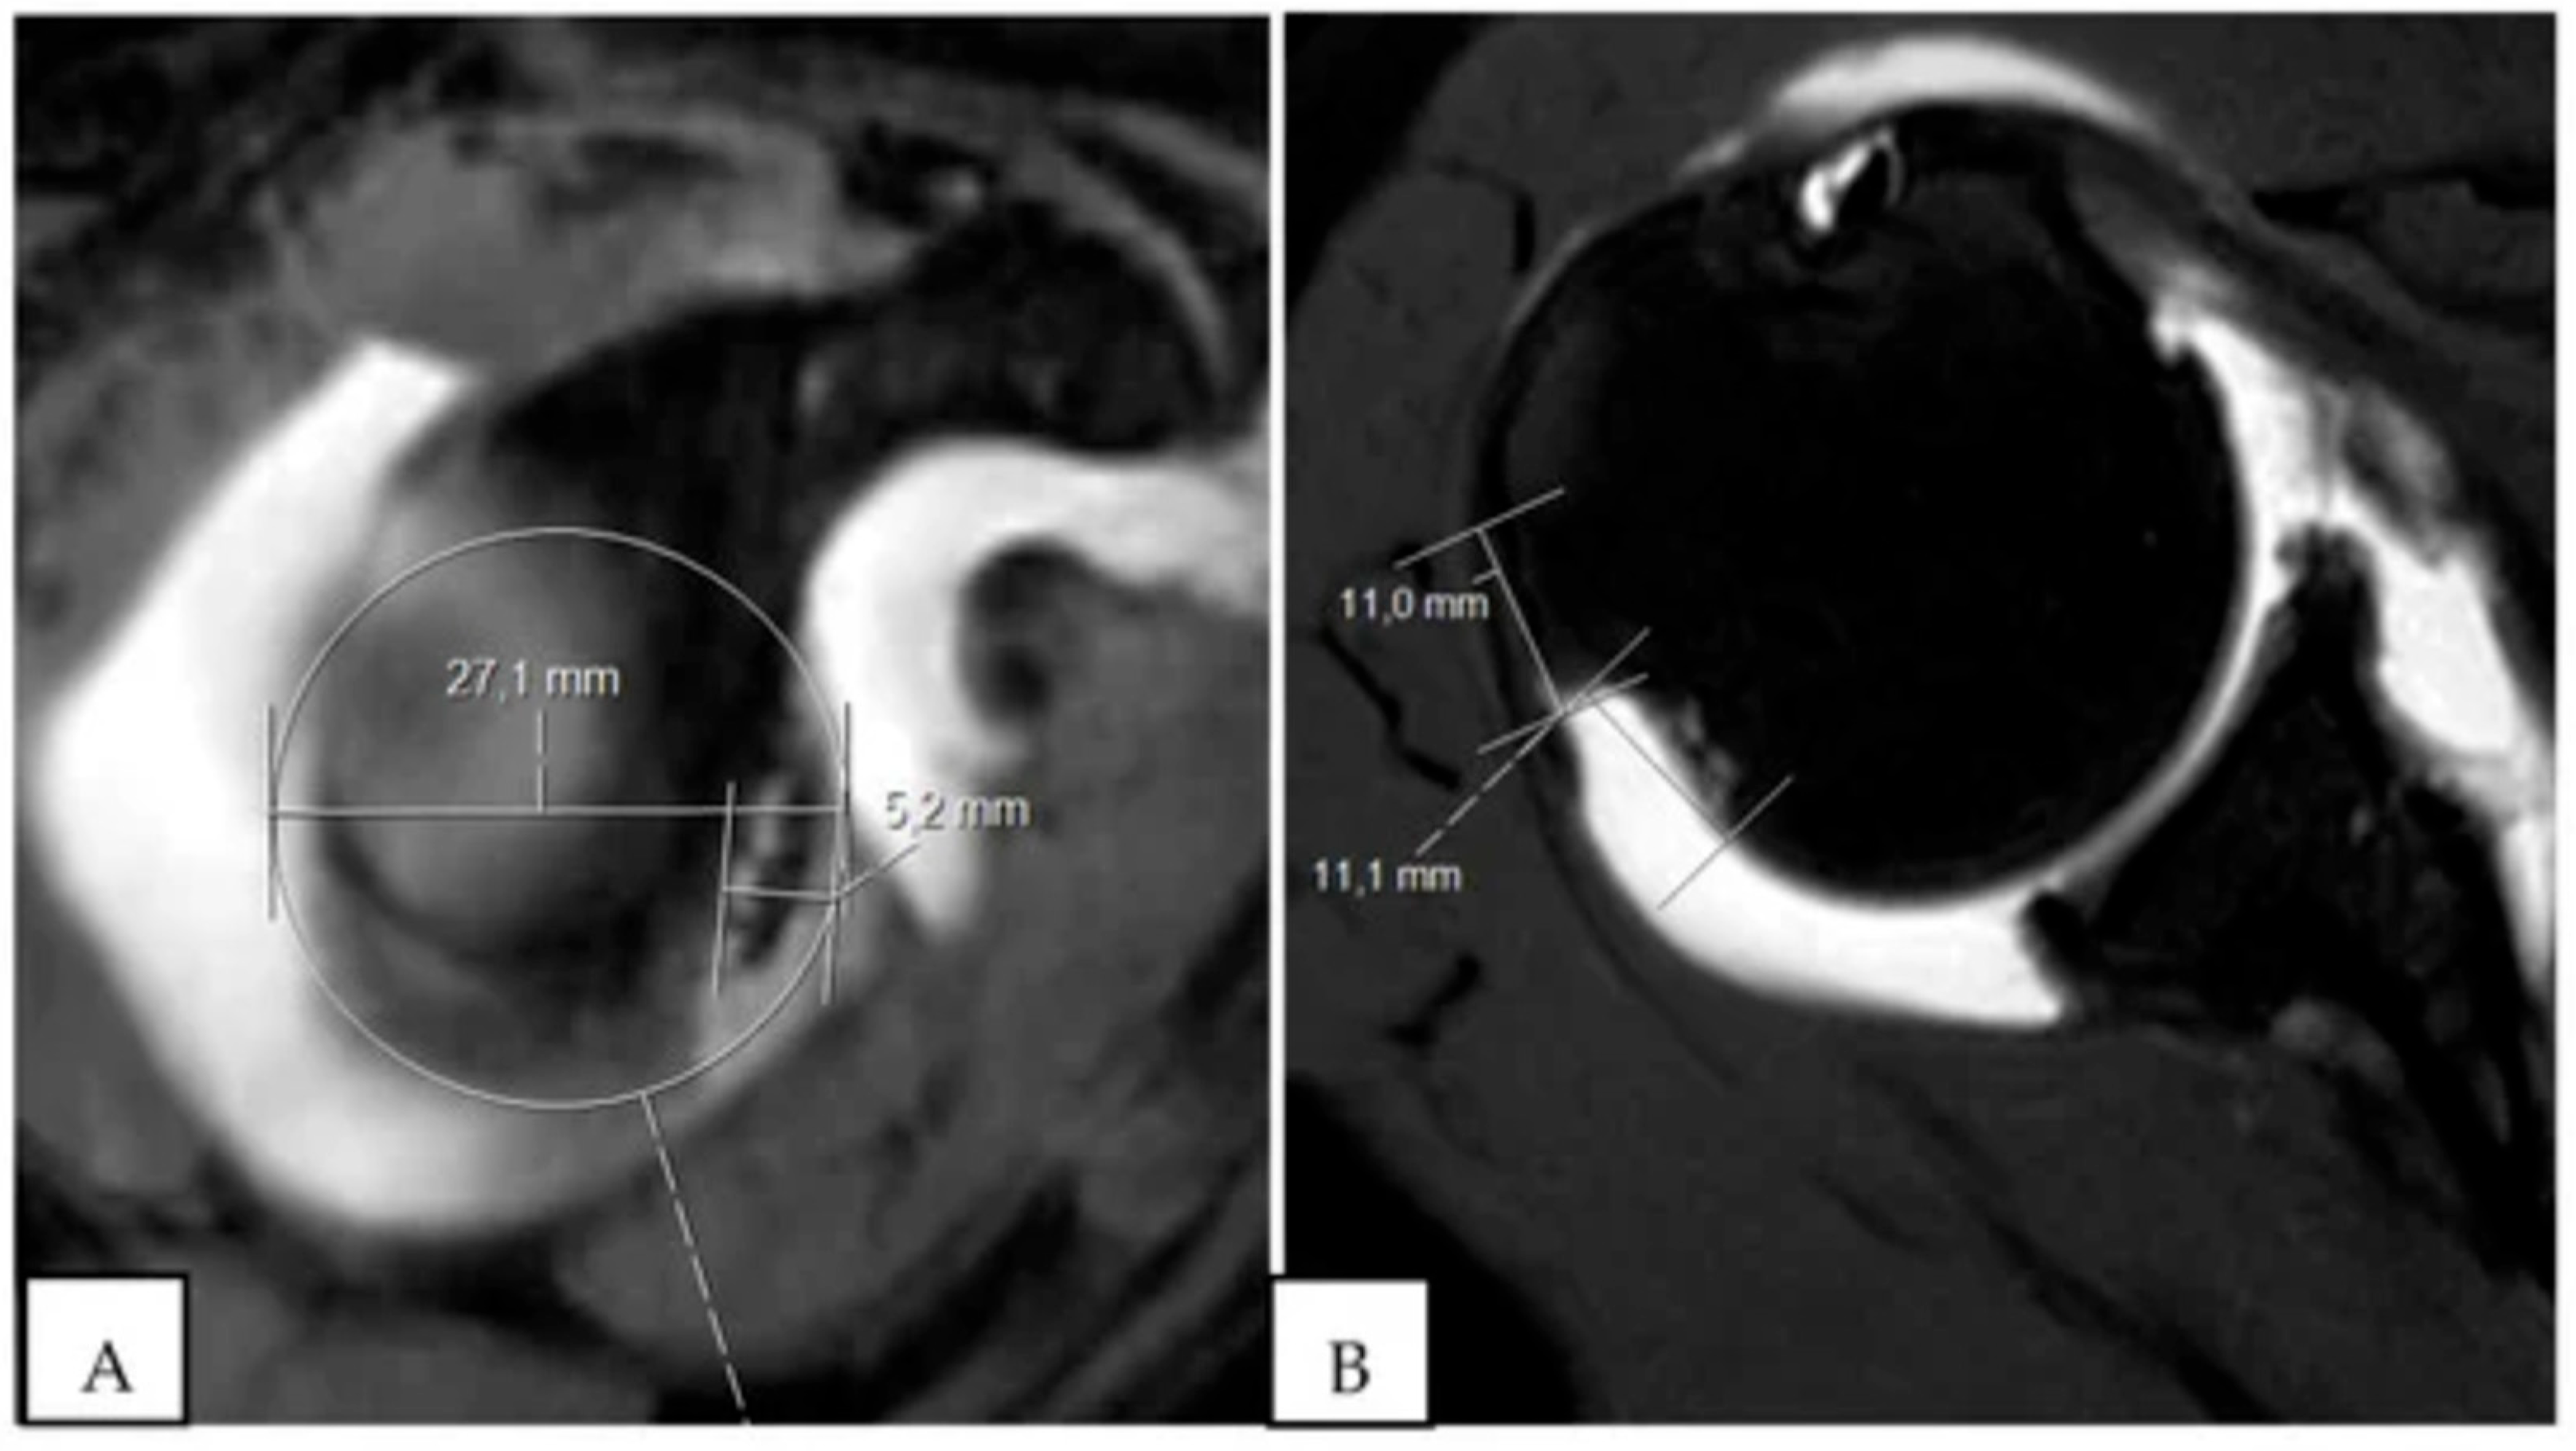

- Gyftopoulos, S.; Beltran, L.S.; Bookman, J.; Rokito, A. MRI Evaluation of Bipolar Bone Loss Using the On-Track off-Track Method: A Feasibility Study. Am. J. Roentgenol. 2015, 205, 848–852. [Google Scholar] [CrossRef] [PubMed]

- Gyftopoulos, S.; Hasan, S.; Bencardino, J.; Mayo, J.; Nayyar, S.; Babb, J.; Jazrawi, L. Diagnostic Accuracy of MRI in the Measurement of Glenoid Bone Loss. Am. J. Roentgenol. 2012, 199, 873–878. [Google Scholar] [CrossRef]

- Makovicka, J.L.; Moore, M.L.; Pollock, J.R.; Rodriguez, M.J.; Shaha, J.S.; Haglin, J.M.; Tokish, J.M. MRI Analysis Demonstrates Improved Reliability in Measuring Shoulder Glenoid Bone Loss Using a Two-Thirds Glenoid Height Technique Compared to the “Best-Fit Circle”. Arthrosc. J. Arthrosc. Relat. Surg. Off. Publ. Arthrosc. Assoc. N. Am. Int. Arthrosc. Assoc. 2023, 40, 666–671. [Google Scholar] [CrossRef]